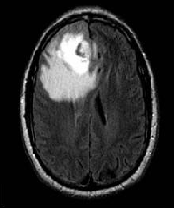

Figure 1: Brain tumour MRI: Magnetic resonance imaging (MRI) of the brain is a safe and painless test that uses a magnetic field and radio waves to produce detailed images of the brain and the brain stem. An MRI scanner consists of a large doughnut-shaped magnet that often has a tunnel in the center. Patients are placed on a table that slides into the tunnel. During the exam, radio waves manipulate the magnetic position of the atoms of the body, which are picked up by a powerful antenna and sent to a computer. The computer performs millions of calculations, resulting in clear, cross-sectional black and white images of the body. These images can be converted into three-dimensional (3-D) pictures of the scanned area. This helps pinpoint problems in the brain and the brain stem when the scan focuses on those areas [3].